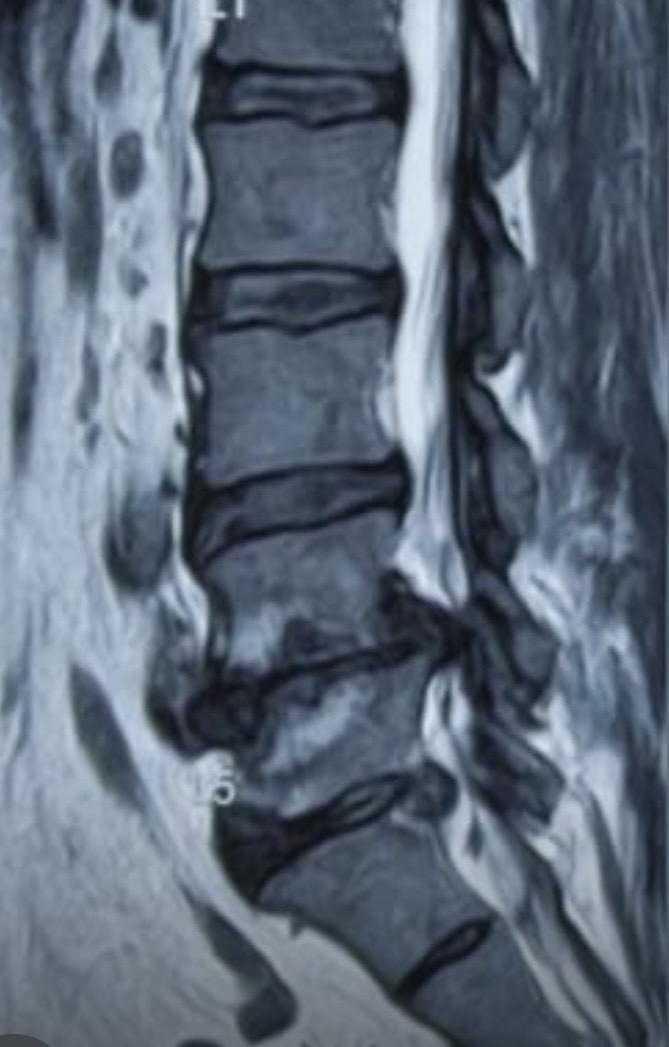

A spinal tumor is an abnormal growth that occurs in the spinal canal or the bones of the spinal column.

Slip disc treatment includes medications, physiotherapy, and in severe cases, surgery to relieve pain and restore normal movement.

A spinal cord injury is damage to the spinal cord that can result in loss of movement, sensation, or function below the affected area.

Spinal tuberculosis is a form of tuberculosis that affects the spine, causing pain, bone damage, and potential spinal deformity if left untreated.